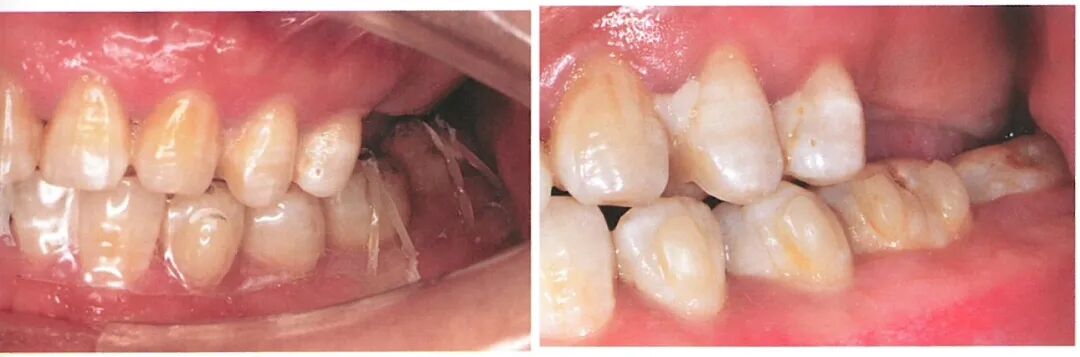

患者的26、27缺失,术前口内检查发现37明显伸长致使修复距离不足。如果只依靠调磨37的方式获得修复空间,调磨量会很大,极可能损伤牙髓。

与患者沟通后,患者选择正畸方式压低对颌牙。我们在26、27 位点植入两颗植体后,患者开始接受隐形矫治配合橡皮圈同时压低36、37。通过正畸压低的方式,患者的36、37与术前相比被明显压低。